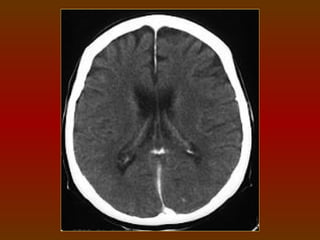

CORTE 7

a) Lobo frontal

b) Corpo do ventrículo lateral

c) Lobo parietal

d) Lobo occipital

e) Giros

f) Sulcos

CORTE 7 a) Lobofrontal b) Corpo do ventrículo lateral c) Lobo parietal d) Lobo occipital e) Giros f) Sulcos